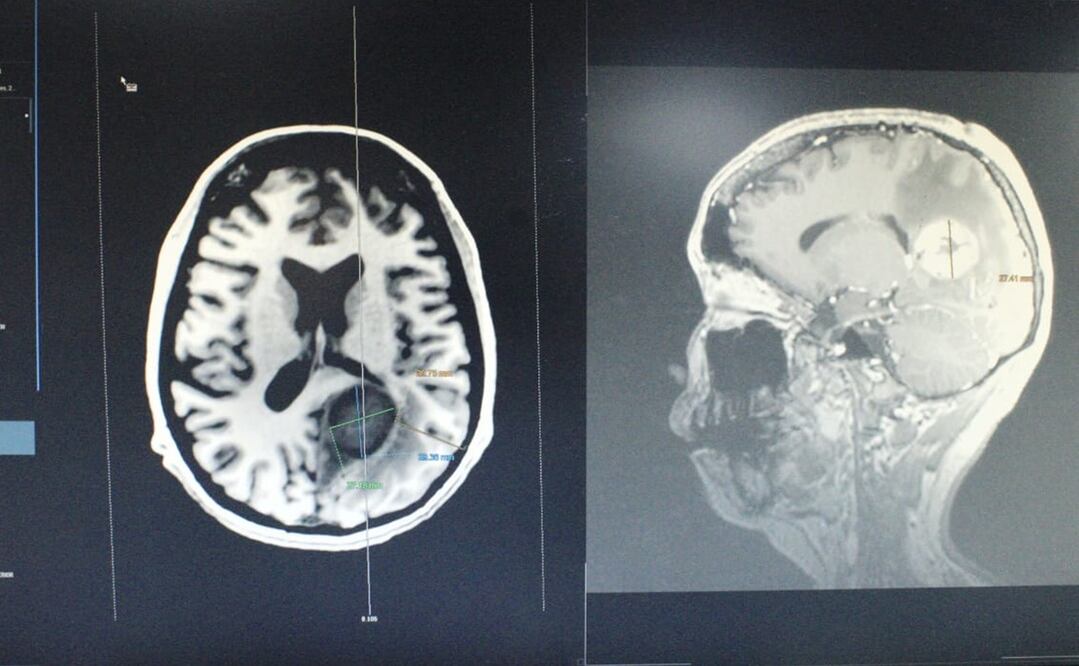

Un grupo multidisciplinario de médicos especialistas del Instituto de Seguridad y Servicios Sociales de los Trabajadores del Estado (ISSSTE) retiraron exitosamente un tumor cerebral maligno del tamaño de un huevo a una mujer de 34 años.

El diagnóstico de la paciente, cuya identidad no fue revelada, era una metástasis de cáncer tipo leiomiosarcoma desarrollado en el corazón. El tumor, informó el ISSSTE comprometía estructuras relacionadas con lenguaje, comprensión, cálculo y función visual.